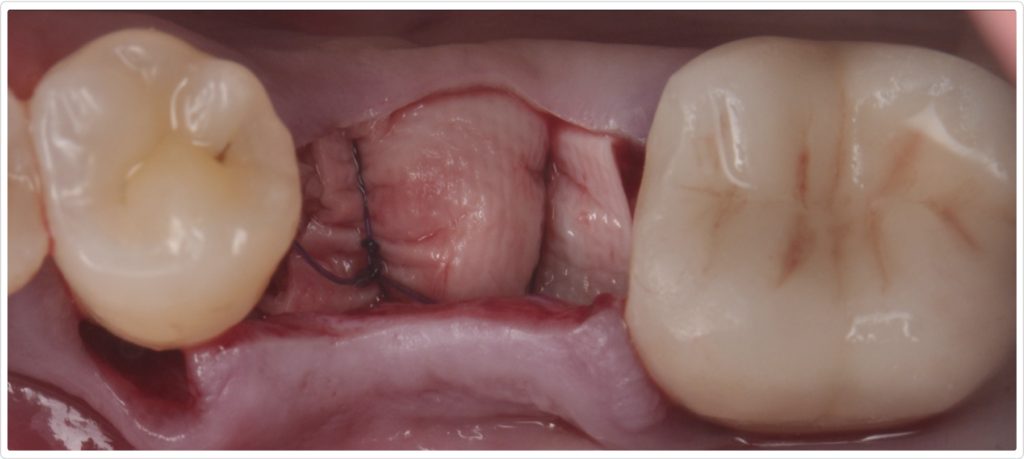

Surgical site closure

The surgical site was meticulously closed using 4-0 PTFE sutures in a horizontal mattress technique, complemented by 6-0 polypropylene simple interrupted sutures in the middle of the ridge to achieve primary closure (Fig. 6). This combination of suturing techniques ensured a stable, secure closure, promoting optimal healing and minimizing the risk of wound dehiscence. Additionally, simple interrupted 4-0 PTFE sutures were used in the interproximal sites.